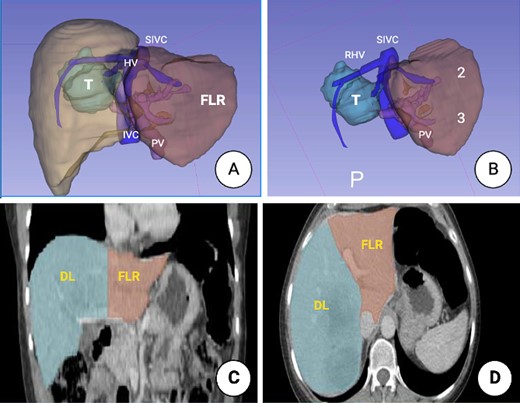

In July 2022, a 49-year-old female, otherwise healthy, presented symptoms of hematochezia and stool caliber changes. A colonoscopy was done, where an exophytic neoplastic lesion was detected on the mucosal surface, measuring around 8 × 3 cm, dark brown, friable and close to obstruction (approximately 70%) at the level of the sigmoid colon, a biopsy of that lesion, pathology reported a moderately differentiated invasive adenocarcinoma originated in the background of a colonic adenoma with high-grade dysplasia. A computed tomography (CT) scan was ordered showing a 7 × 3 cm mass in the sigmoid colon as well as a couple of lesions in the liver in segments 5, 6, 7 and 8, consistent with metastasis. A radical resection of the primary cancer with a left hemicolectomy was with primary anastomosis. After recovering from surgery, the patient was considered for systemic treatment based on eight cycles of oxaliplatin and capecitabine. A new CT scan showed two liver lesions measuring 5 and 6 cm, occupying segments 5, 6, 7, and 8, in addition to at least two other smaller lesions in segments 6 and 7, with no abnormal enhancement under contrast. A liver magnetic resonance imaging (MRI) (June 2023) showed the same lesions corresponding to metastatic deposits, conditioning dilation of the intrahepatic bile duct mainly on its right posterior branch (Fig. 1).

CT scan images. (A) Coronal plane showing the tumor location involving segments 5, 6, 7 and 8. (B) Axial plane showing the relation to the inferior vena cava (IVC). (C) MRI showing a liver mass with peripheral and heterogeneous central enhancement. (D) Axial MRI (T1phase). Ao, aorta; S, spleen.